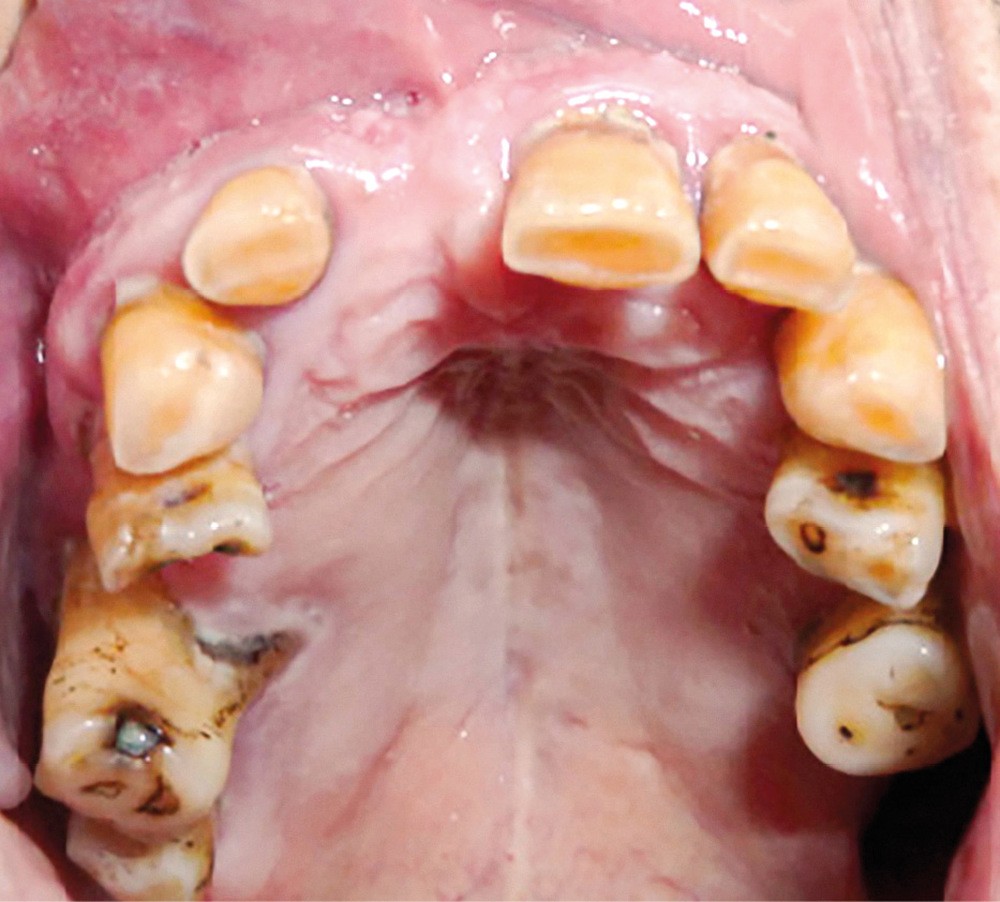

L’examen intra-oral montre un comblement au fond du vestibule au niveau de tout le secteur antérieur depuis l’incisive centrale gauche (21) jusqu’à la première prémolaire droite (14), la muqueuse est d’aspect sain (fig. 4). La palpation vestibulaire haute révèle une masse élastique sous-muqueuse située au niveau du plancher nasal antérieur, dépressible et légèrement douloureuse.

L’origine dentaire a été écartée par la clinique (aucun antécédent de douleurs dentaires et le test de vitalité pulpaire est positif sur les dents antérieures) et par l’orthopantomogramme, qui n’a révélé aucune modification des structures osseuses.